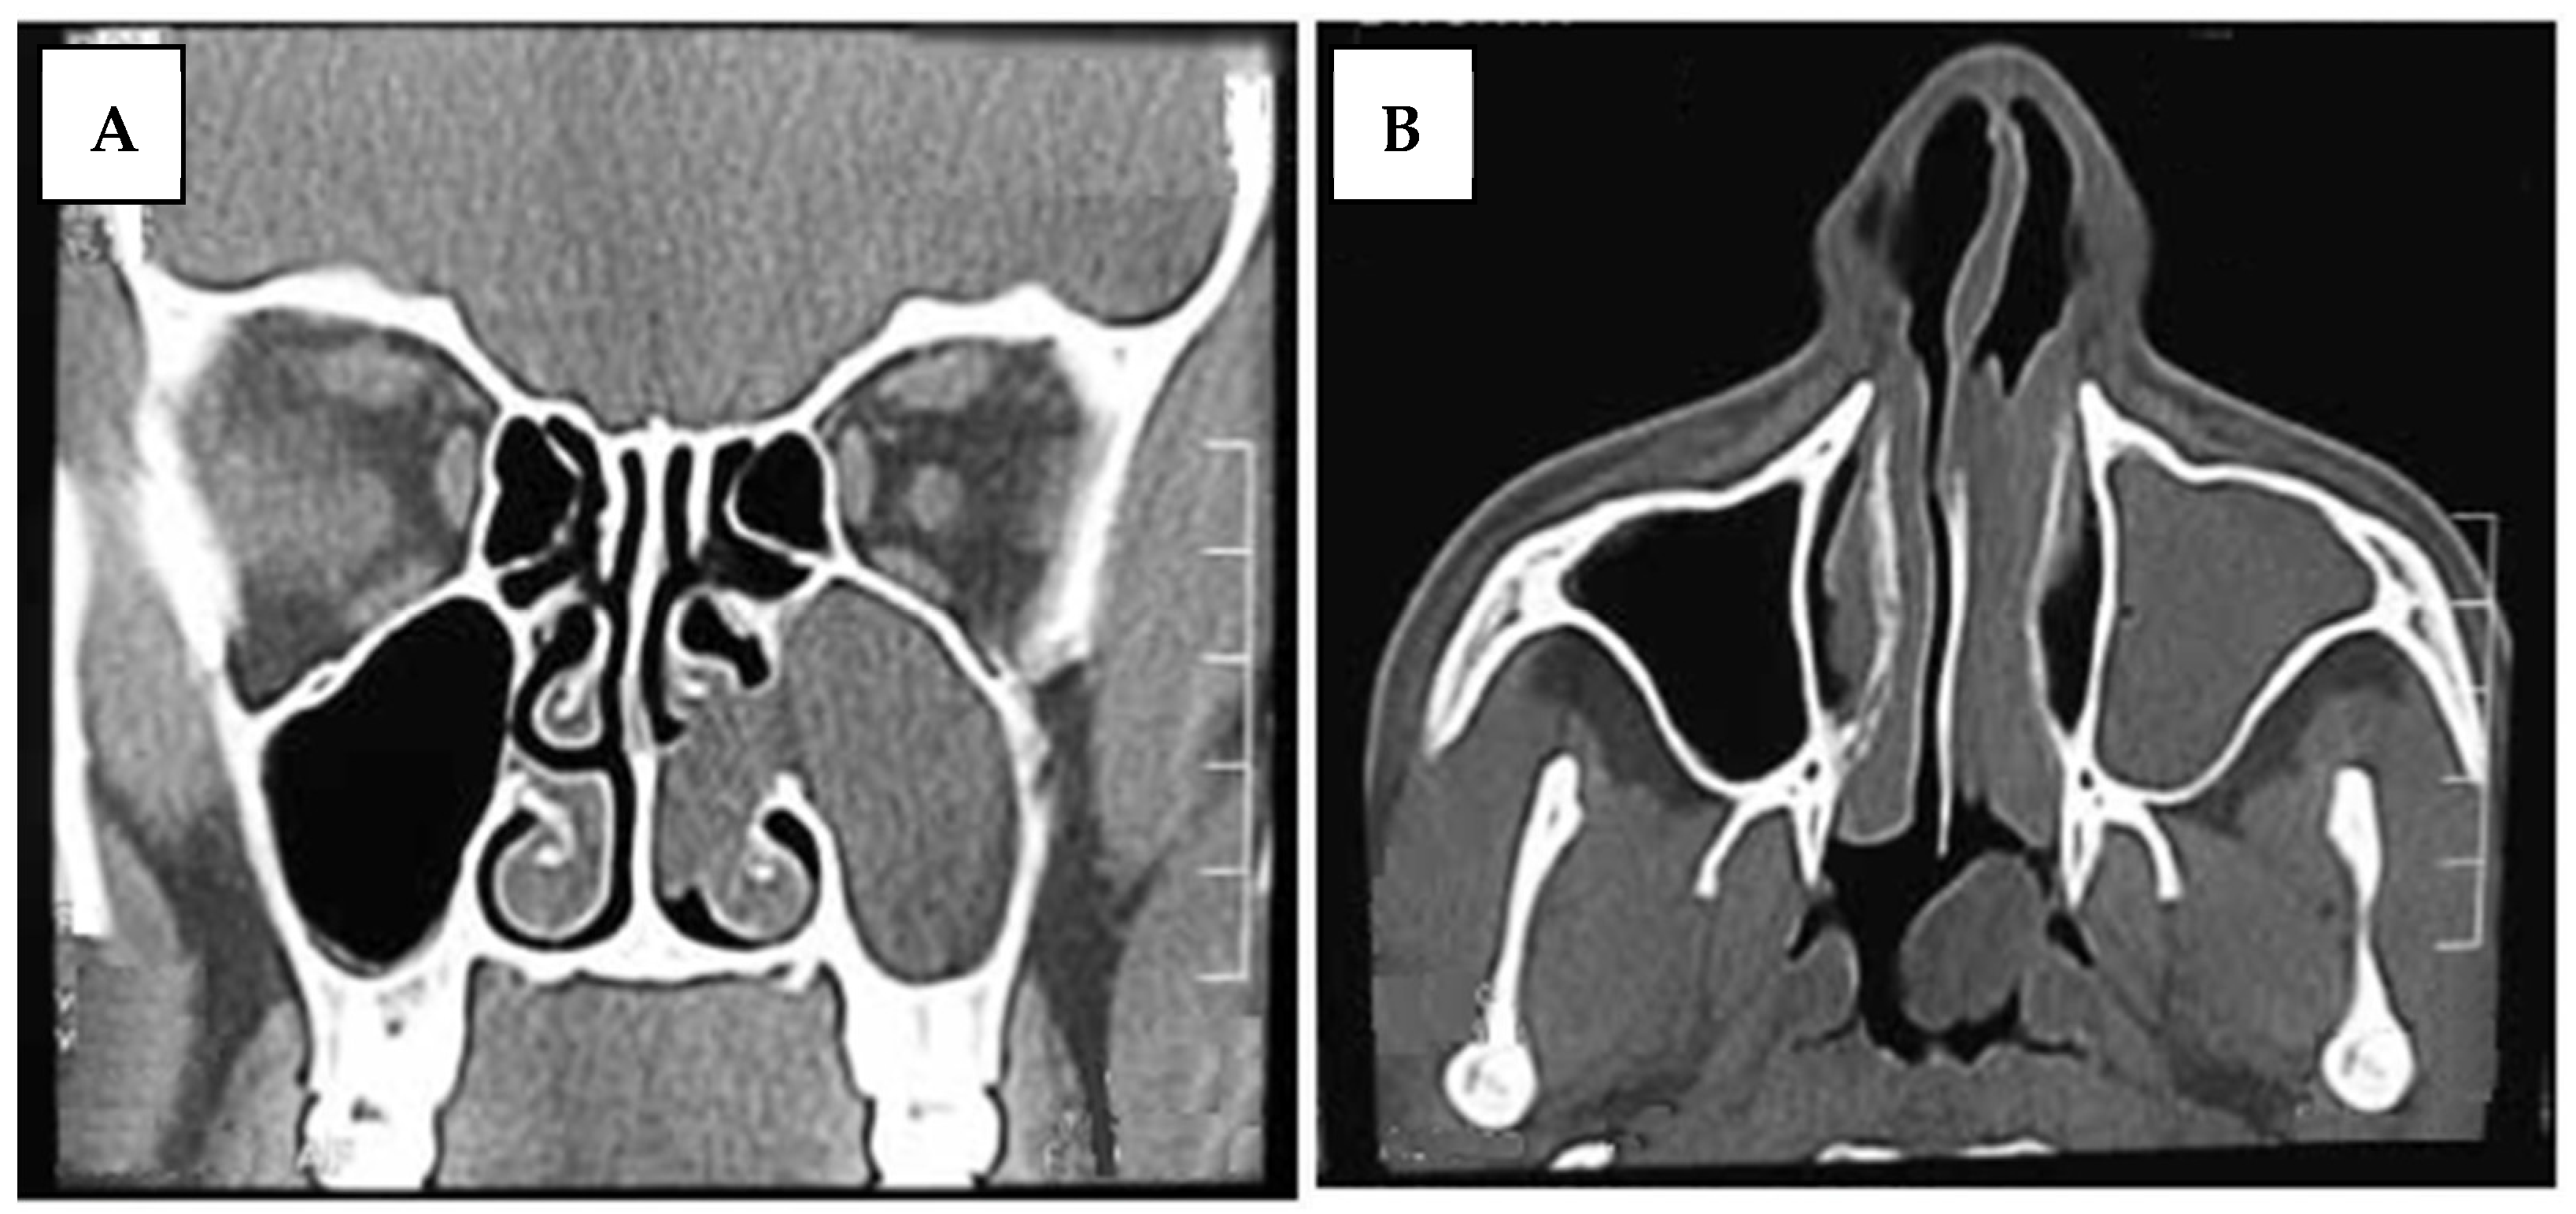

Surgical Technique